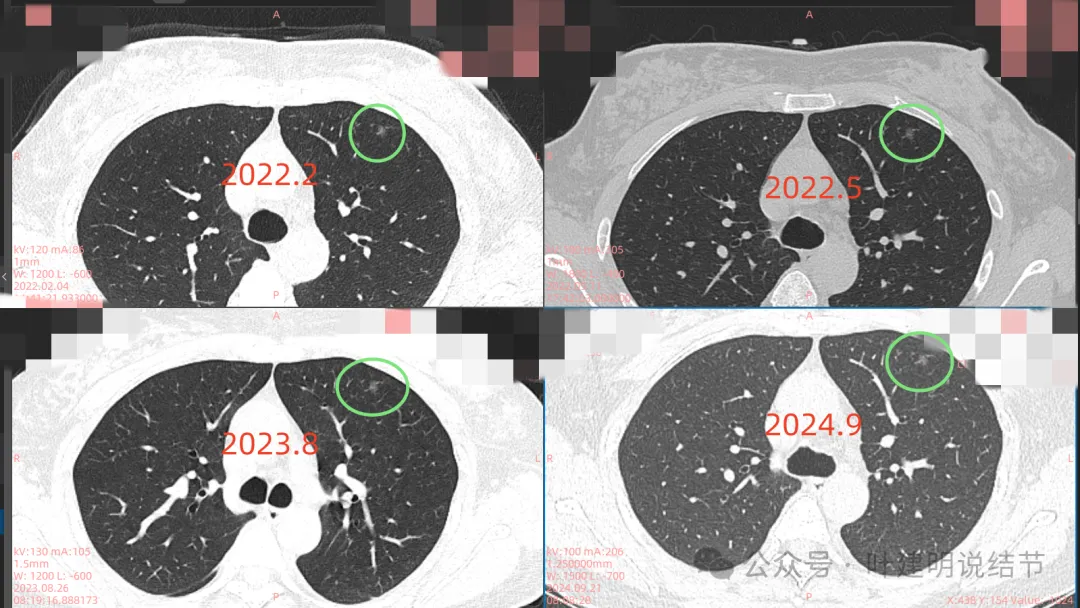

右中叶病灶也是淡的磨玻璃密度,瘤肺边界稍显不清,密度不是太均匀。大概是肺泡上皮增生或不典型增生之类的可能性,也可能慢性炎伴少许纤维增生。

再看2022年5月时的影像:

这时B医院医生主张手术时的情况:

三处病灶均仍在,间隔3个月显然说不上明显进展或变化。这时候问诊我,我对比后认为风险仍低,能再随访,结友停掉了本已经预约的手术。

再看2023年8月时复查的影像:

有变化吗?说不上!

最后来看2024年9月,也就是叫停手术后2整年之后复查的情况:

仍说不上有明显进展,如果将这几次的放在一起来对照,就会更加直观:

病灶基本上没有明显变化。当然不必过于在意具体大小有没有几毫米的差别,也不必在意具体CT值有几十或百把的区别,微细的差别不影响临床决策,也就是说改变都不足以让肉眼发现的,怎么会影响预后呢!

我看了你2022年2月时的片子,以及某医院建议你手术说有进展时的2022年5月时的片子和2023年8月复查时的片子,再对比2024年9月时的影像,总体上明显点的病灶仍是这三处。首先均仍是纯磨,有的似有微血管进入或穿行,但磨玻璃成分密度很淡,而且大小无明显进展。至于右上病灶是否有缩小好转,感觉上右上的与右中叶的都略显淡了点,我怀疑还是扫描条件不一的关系,本身又是非常小而淡的病灶,可比性稍差,并不能说明必是有吸收好转。但肯定说不上有进展,风险仍是低的,半年或一年复查随访(个人倾向可以年度复查)总归不至于会耽误病情。意见供参考!